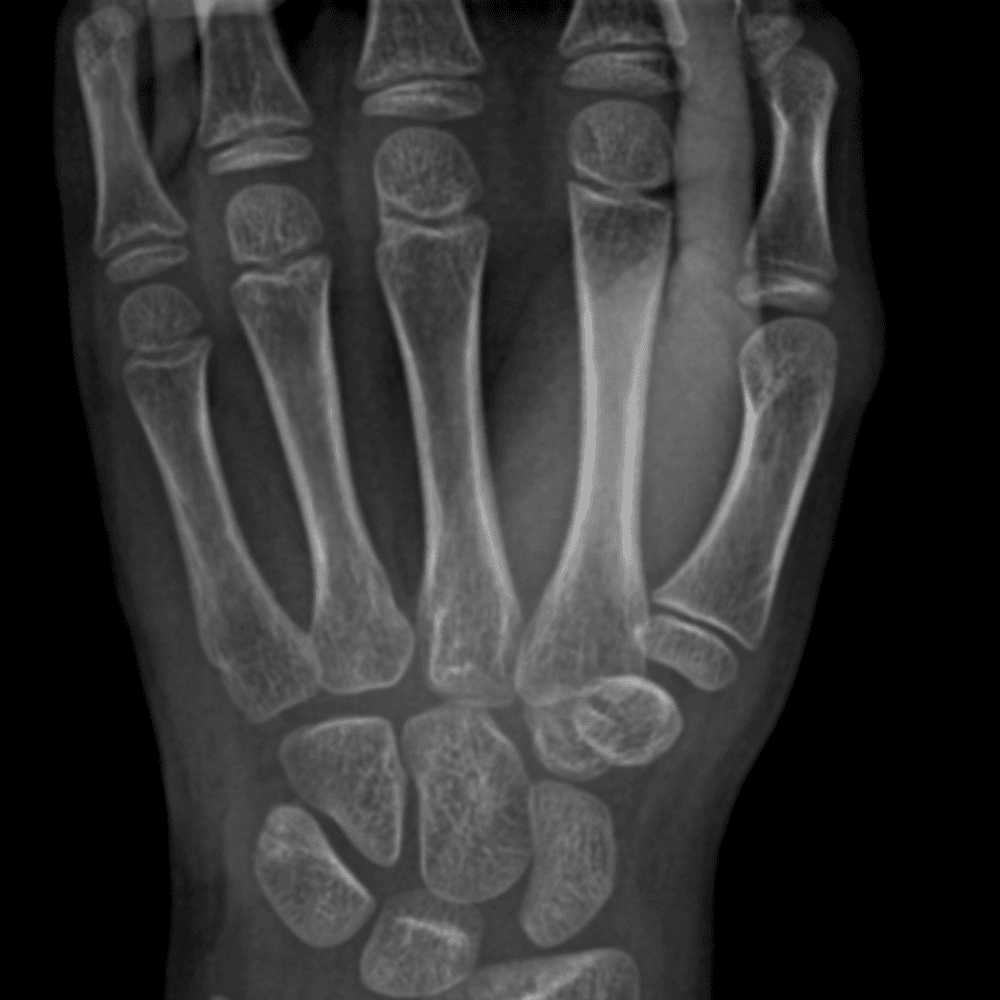

Simulates call by including subtle or difficult cases and some normals.

30 cases